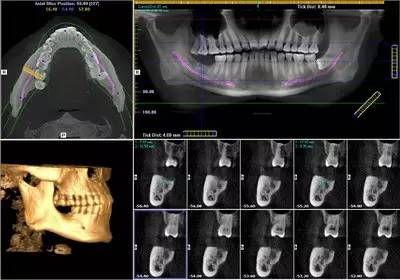

由于XG 3D/Ceph分辨率高,可以分辨人體組織內(nèi)細微的差別,使影像診斷的范圍大大擴大。尤為重要的是8*8cm視野的掃描一次即可對口腔上下頜全部的組織及上頜竇腔及下頜神經(jīng)管結(jié)構(gòu)進行重建,為出診患者的綜合觀察及常規(guī)攝影提供了支持。